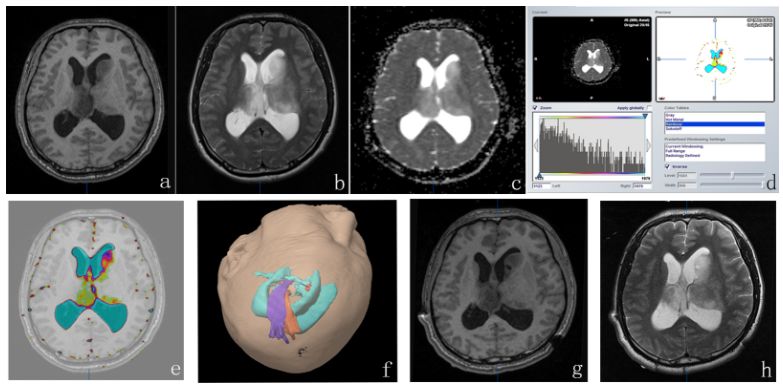

研究回顾性分析60名应用ADC导航引导下穿刺活检、术后病理诊断为胶质瘤WHO2、3级的患者。记录穿刺靶点的FA值和ADC值,应用iPlan 3.0(BrainLAB公司,德国)制定穿刺活检计划,在VarioGuide(BrainLAB公司,德国)活检系统下实施活检,使用术中磁共振确认活检位置(图1)。将穿刺活检标本的病理结果作为金标准,绘制受试者工作特征曲线(ROC)评估各指标的灵敏度、特异度、准确度、阳性预测值、阴性预测值和曲线下面积(AUC),此外应用所有诊断指标建立诊断预测模型,并评估其诊断效能(图2)。

图1. ADC影像引导穿刺活检流程(24岁男性,主诉头痛半月)。a-c:术前T1、T2以及ADC图显示病变位于左侧尾状核头;d: 应用Brainlab iplaning 3.0将ADC灰度图转换为伪彩图;e: 将ADC伪彩图与T1WI解剖像进行融合(ADC伪彩图中,低ADC值显示为热点区域,标记为红色穿刺靶点);f: 活检计划(穿刺路径(深蓝色)避开重要侧脑室(浅蓝色)、锥体束(紫色)和皮质脊髓束(橙色)达到穿刺靶点(红色));g-h: 术中T1、T2影像显示靶点穿刺成功。